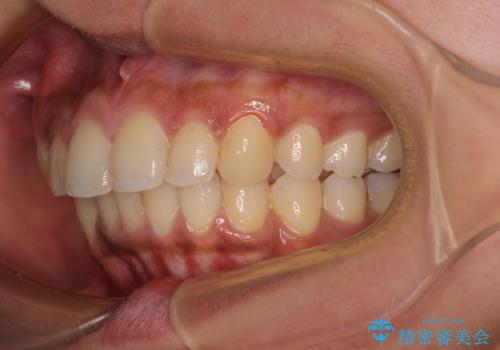

深い咬み合わせと前歯のデコボコ インビザラインによる矯正治療

- 前歯のデコボコと、食いしばりやすい咬み合わせを気にして来院された患者様です。

骨格的に下顎骨が左側に偏位しており、インビザラインでの矯正治療では奥歯の咬みにくさが残る仕上がりが懸念されましたが、新幹線での通院となるため、来院回数の少ないインビザラインでの治療を希望されました。

リスクをご説明した上で、インビザラインにより気になっている叢生と深い咬み合わせを改善していくこととしました。

治療途中では、左右ともに奥歯が咬みにくい状態が続き、問題なく噛めるようになるまでに長期間を要しました。

一方で、デコボコや下顎の前歯が隠れてしまうほどの深い咬み合わせはしっかりと改善されました。